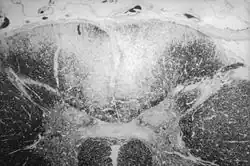

Axial section of the spinal cord showing syphilitic destruction (whitened area, upper center) of the posterior columns which carry sensory information from the body to the brain

Tabes dorsalis is a late consequence of neurosyphilis, characterized by the slow degeneration (specifically, demyelination) of the neural tracts primarily in the dorsal root ganglia of the spinal cord (nerve root). These patients have lancinating nerve root pain which is aggravated by coughing, and features of sensory ataxia with ocular involvement.

Tabes dorsalis is caused by demyelination by advanced syphilis infection (tertiary syphilis) when the primary infection by the causative spirochete bacterium, Treponema pallidum, is left untreated for an extended period of time (past the point of blood infection by the organism).[3] The spirochete invades large myelinated fibers, leading to the involvement of the dorsal column medial leminiscus pathway rather than the spinothalamic tract.